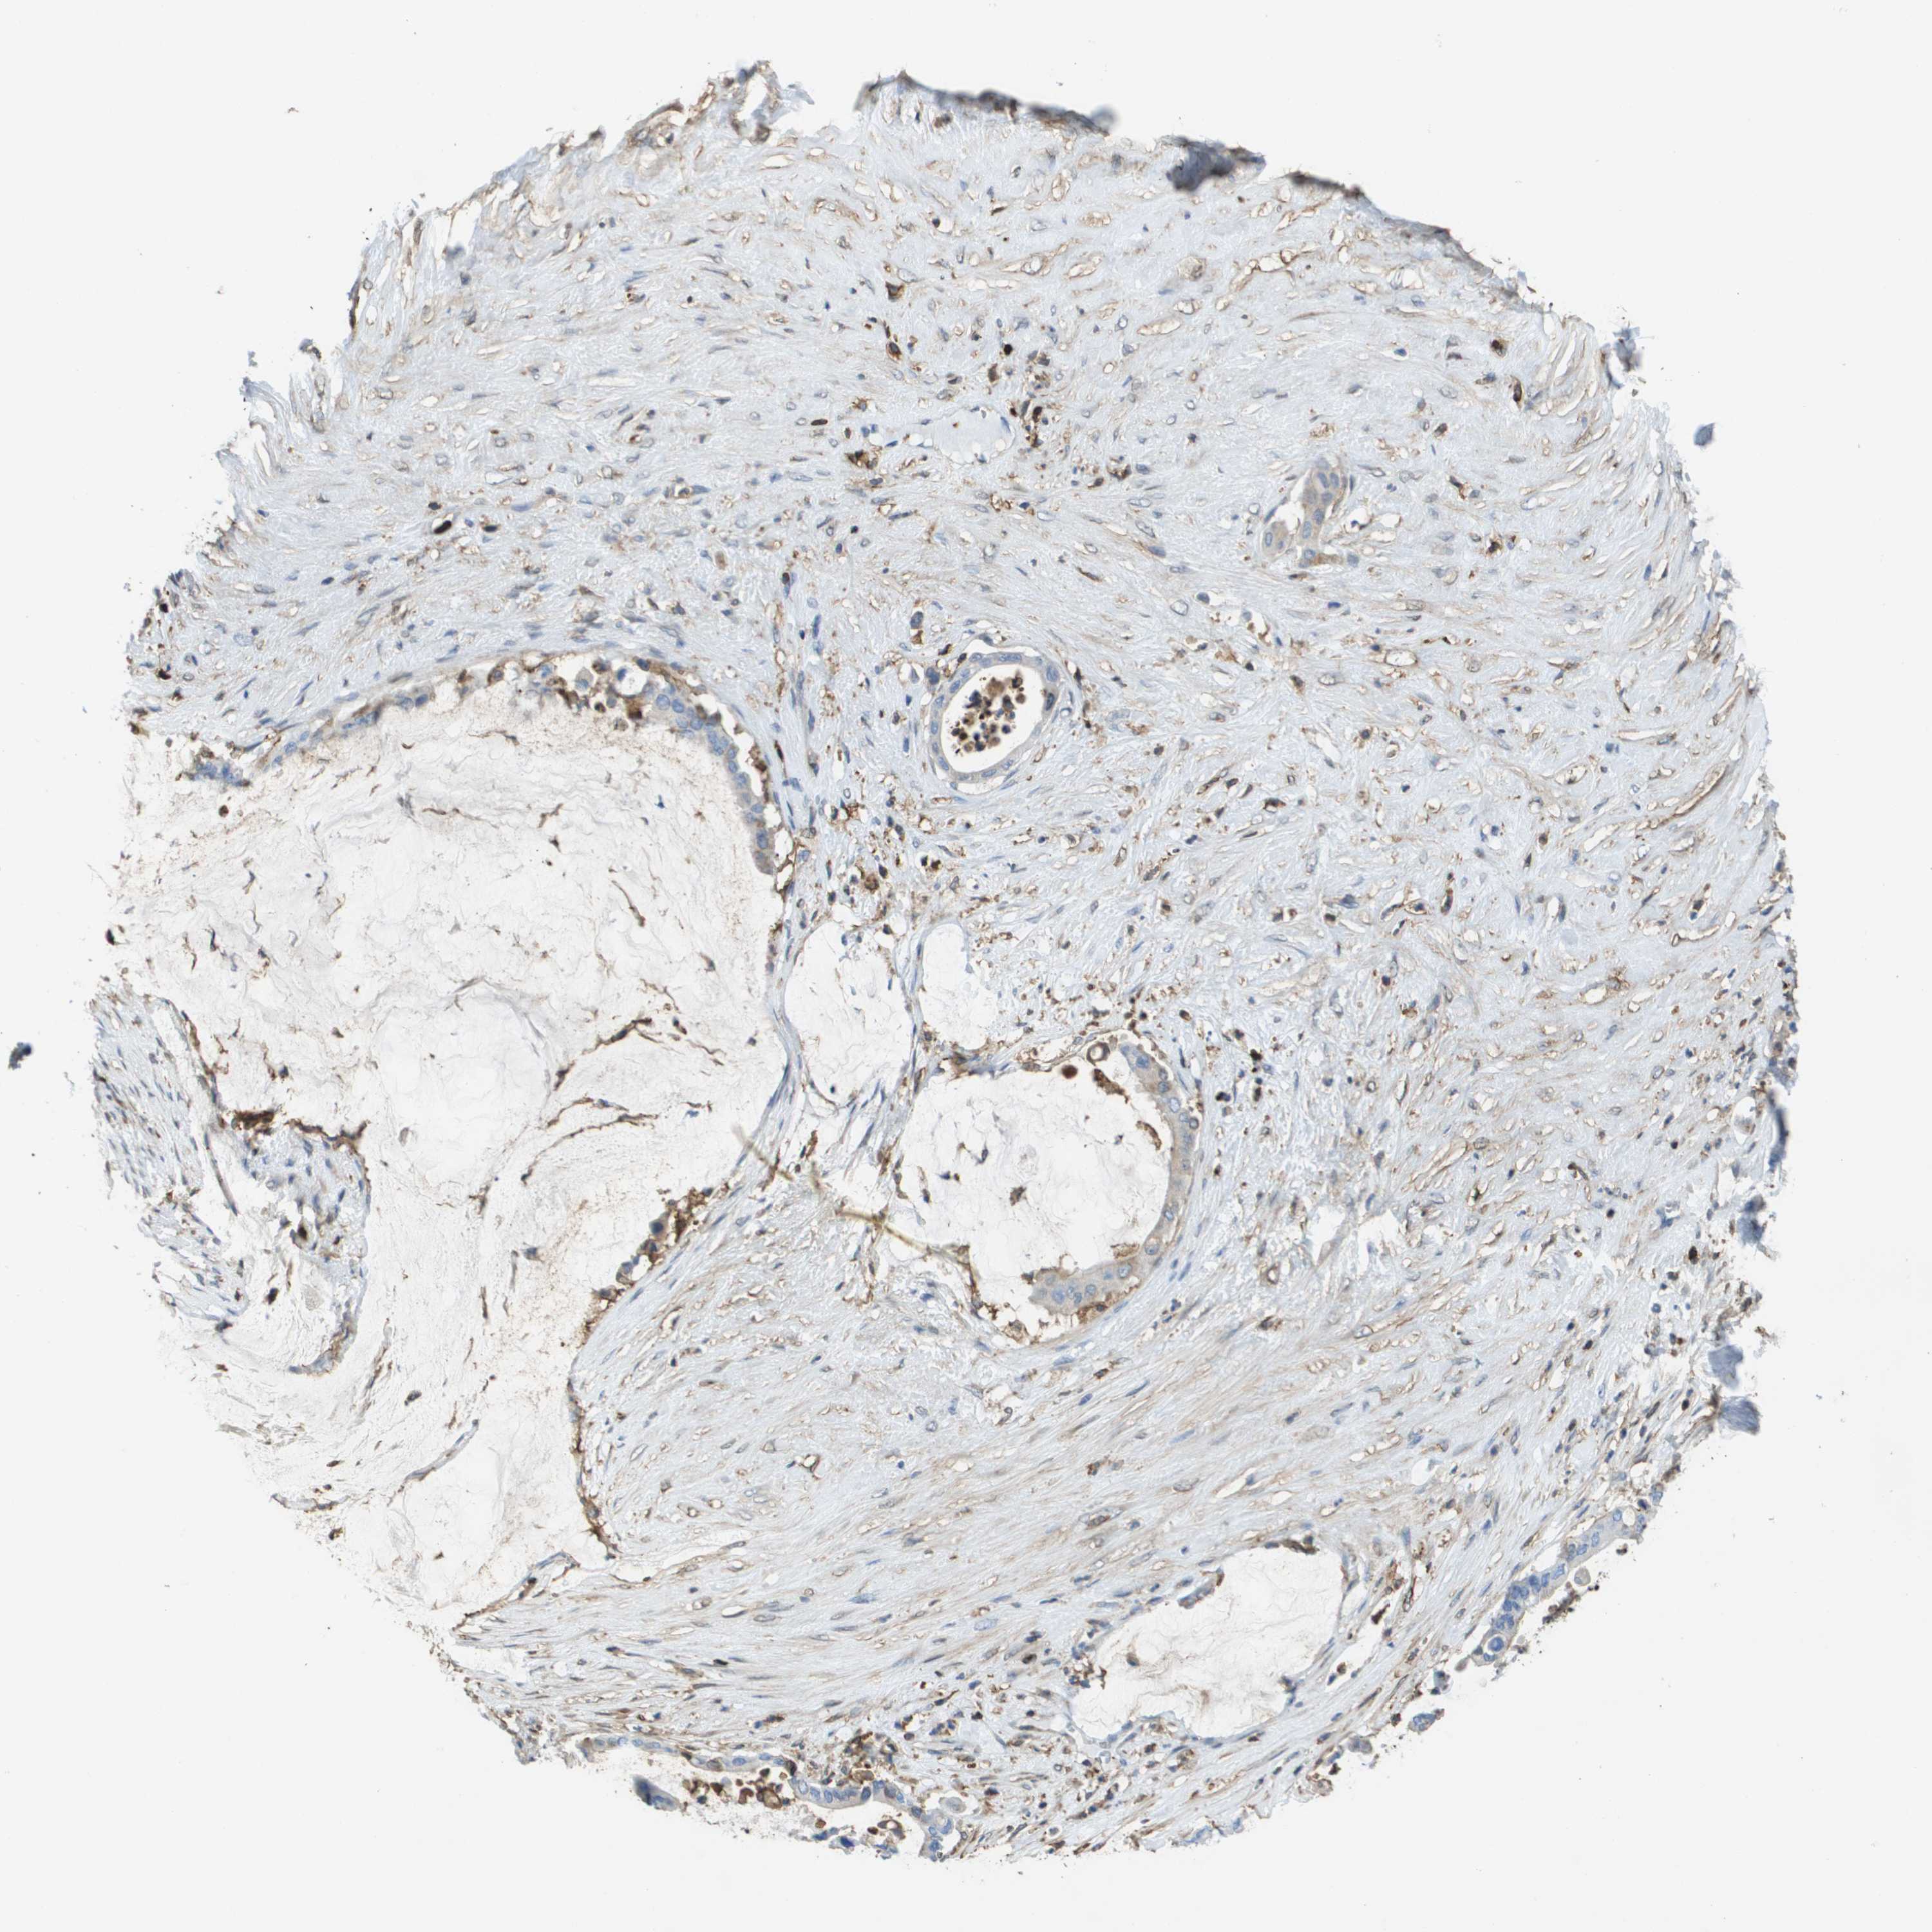

PANCREATIC CANCER - Protein expressioni

A mouse-over function shows sample information and annotation data. Click on an image to view it in a full screen mode. Samples can be filtered based on level of antibody staining by selecting one or several of the following categories: high, medium, low and not detected. The assay and annotation is described here.

Note that samples used for immunohistochemistry by the Human Protein Atlas do not correspond to samples in the TCGA dataset.

Antibody stainingi

Antibody staining in the annotated cell types in the current human tissue is reported as not detected, low, medium, or high, based on conventional immunohistochemistry profiling in selected tissues. This score is based on the combination of the staining intensity and fraction of stained cells.

Each image is clickable and will lead to virtual microscopy that enables deeper exploration of all samples and also displays staining intensity scores, fraction scores and subcellular localization as well as patient and tissue information for each sample.

Antibody HPA016450

Antibody HPA021079

Staining

High

Medium

Low

Not detected

Intensity

Strong

Moderate

Weak

Negative

Quantity

>75%

75%-25%

<25%

None

Location

Nuclear

Cytoplasmic/membranous

Cytoplasmic/membranous,nuclear

Adenocarcinoma, NOS